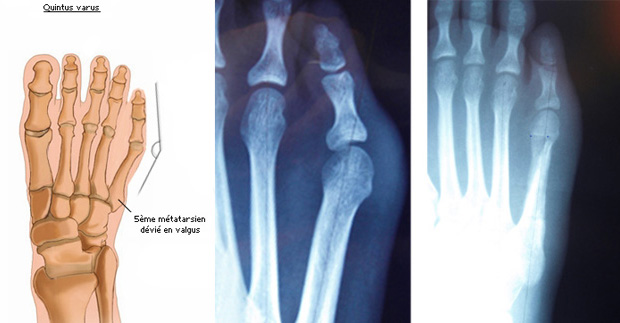

La bosse externe de la tête du 5ème métatarsien (quintus varus) sera traitée par une ostéotomie (section osseuse) du 5ème métatarsien, parfois associée à un geste de plastie cutanée et un allongement du tendon extenseur.